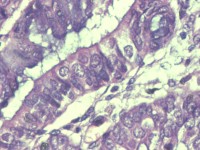

性别

女

年龄

55岁

临床诊断

异常子宫出血

一般病史

阴道不规则出血1月

标本名称

子宫内膜

大体所见

灰白色组织1堆、4*3.4*2.2CM大。

能诊断癌吗

子宫内膜样腺癌